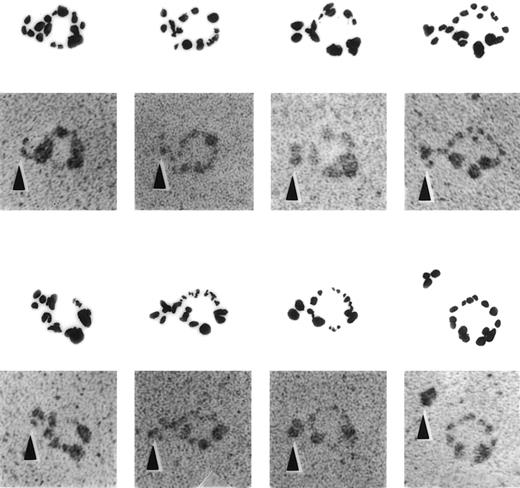

Several approaches were used to determine whether defensin forms complexes with Lp(a), the portion(s) of the lipoprotein involved, and the capacity of such complexes to bind to matrix. Formation of complexes between defensin and Lp(a) was evident by immunoelectron microscopy (Fig 4). Anti-defensin antibody bound to Lp(a) particles preincubated with defensin were readily detected, whereas no binding of the antibodies to Lp(a) alone was seen in this case (Fig 4) or when nonimmune sera was incubated with defensin/Lp(a) mixtures (not shown).

ImmunoEM appearance of defensin/Lp(a) complex. Electron micrographs of defensin/Lp(a) complexes. Lp(a) was incubated alone or in the presence of 1:10 molar ratio of defensin for 30 minutes at 22°C followed by incubation with anti-defensin sera for 30 minutes at 22°C. All specimens were rotary shadowed with tungsten. A gallery of selected examples of individual Lp(a) molecules attached to anti-defensin antibody in the presence and absence (lower panel, far right) of defensin is shown. No binding was seen when nonimmune sera was substituted for anti-defensin sera. The arrows denote the location of the anti-defensin antibodies.

Rotary-shadowed samples were prepared by spraying a dilute solution of protein (final concentration, ∼40 μg/mL) in a volatile buffer (0.05 mol/L ammonium formate at pH 7.4) and 70% glycerol onto freshly cleaved mica and shadowing with tungsten followed by deposition of a carbon film in a vacuum evaporator (Denton Vacuum Co, Cherry Hill, NJ).67 68 Ratios of Lp(a) to defensin were generally 1:10 or 1:22, and samples were incubated for 30 minutes at 22°C. A 10× excess of rabbit anti–HNP-1 sera was incubated for an additional 30 minutes at 22°C. All experiments were repeated several times and many micrographs were taken of randomly selected areas to ensure that the results were reproducible and representative. All of the specimens were examined in a Philips 400 electron microscope (Philips Electronic Instruments Co, Mahwah, NJ), usually operating at 80 kV.